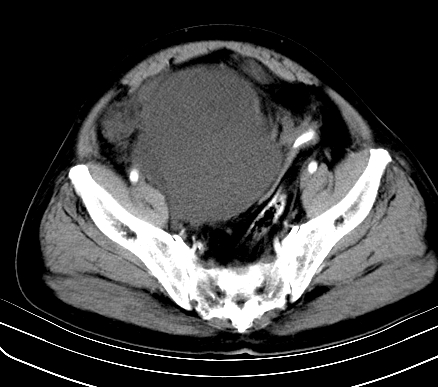

标题: CT19729B:男,74岁,因腿疼就诊,查体触腹部肿物,

增强扫描

动脉期

【ct表现】

1、肿块巨大,往往位于腹膜后,长大后才引起症状而就诊;那么位于腹膜后的肿瘤80%为恶性肿瘤。

2、实性肿瘤,增强扫描轻度不均强化,实性肿瘤一般不是好东西。

3、肿瘤边缘似见少许脂肪样密度。

4、腹膜后未见肿大淋巴结,但肿瘤于临近的肠管及组织接触紧密。

【诊断】

腹部占位,考虑位于腹膜后的恶性肿瘤,脂肪肉瘤(实体型)可能性大。